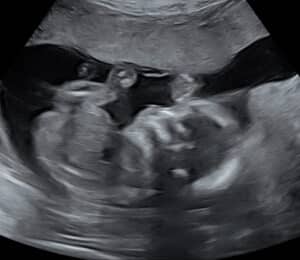

reversing-burned-tubes-Poteau-OKWe are halfway there with our baby boy!

A big thank you to Dr. Monteith! 💙

Patient age: 35

Tubal ligation type: Coagulation (burned)

Patient hometown: Poteau, Oklahoma